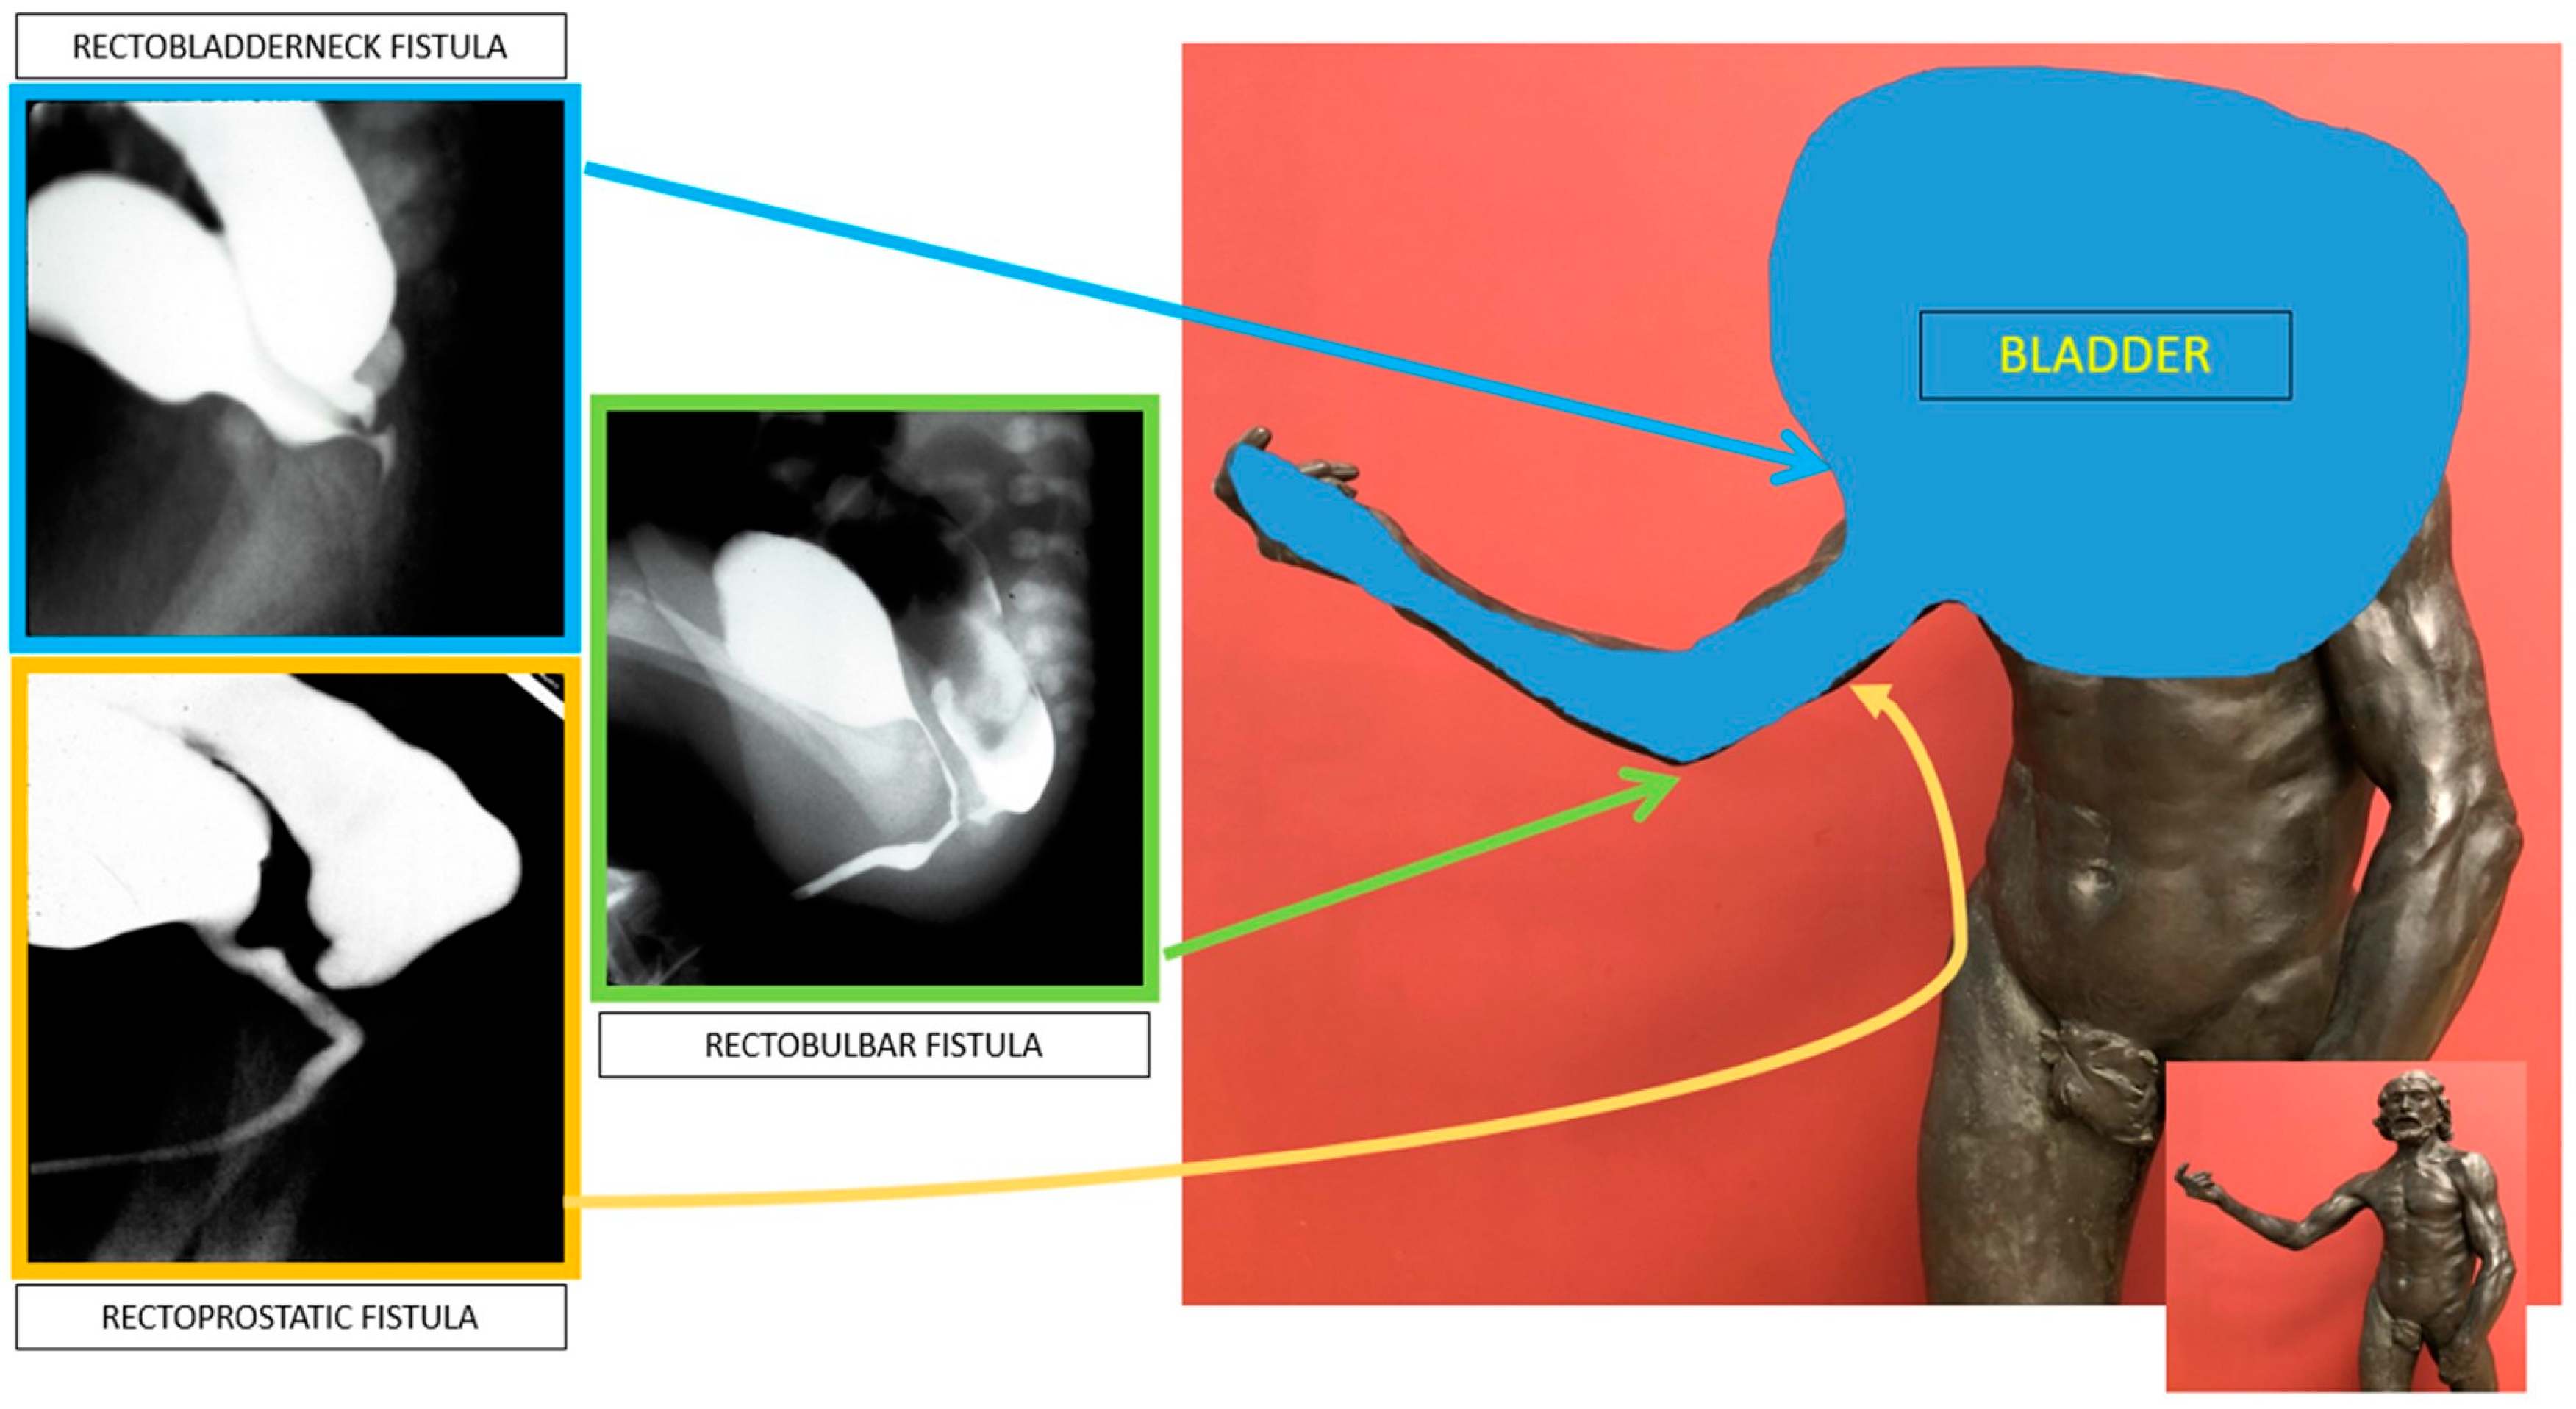

The collaborative model has led to a protocolized description of the anatomic options for patients with anorectal malformations. The anatomy influences the operative approach chosen and the clinical outcomes expected [Figure 4] [38]. A distal colostogram is vital for defining the location of the rectourethral fistula and the rectum for surgical planning of either a laparoscopic approach or a perineal (posterior sagittal) approach to find the rectum, thereby avoiding injury to the urethra. For Hirschsprung disease, a good contrast study helps the surgeon predict the location of the expected transition zone and properly plan the pull-through.

Figure 4. Defining the anatomy for rectourethral fistulae utilizing the analogy of an arm to represent specific anatomic locations.